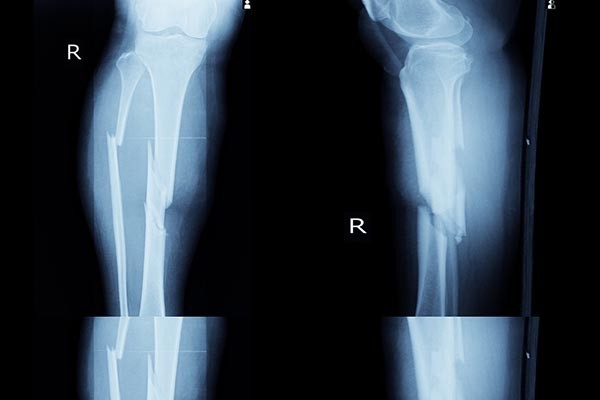

Angolkór, csontlágyulás: tünetei, vizsgálata és kezelési lehetőségei

Az angolkór vagy rachitis a fiatal, gyorsan növekvő szervezet kalcium- és foszforanyagcseréjének összetett zavara, melyet elsősorban a D-vitamin hiánya okoz. Ritkább formája a kalcium- vagy foszforhiány okozta rachitis. A betegség felnőttkorban jelentkező formáját oszteomaláciának (csontlágyulásnak) nevezzük.